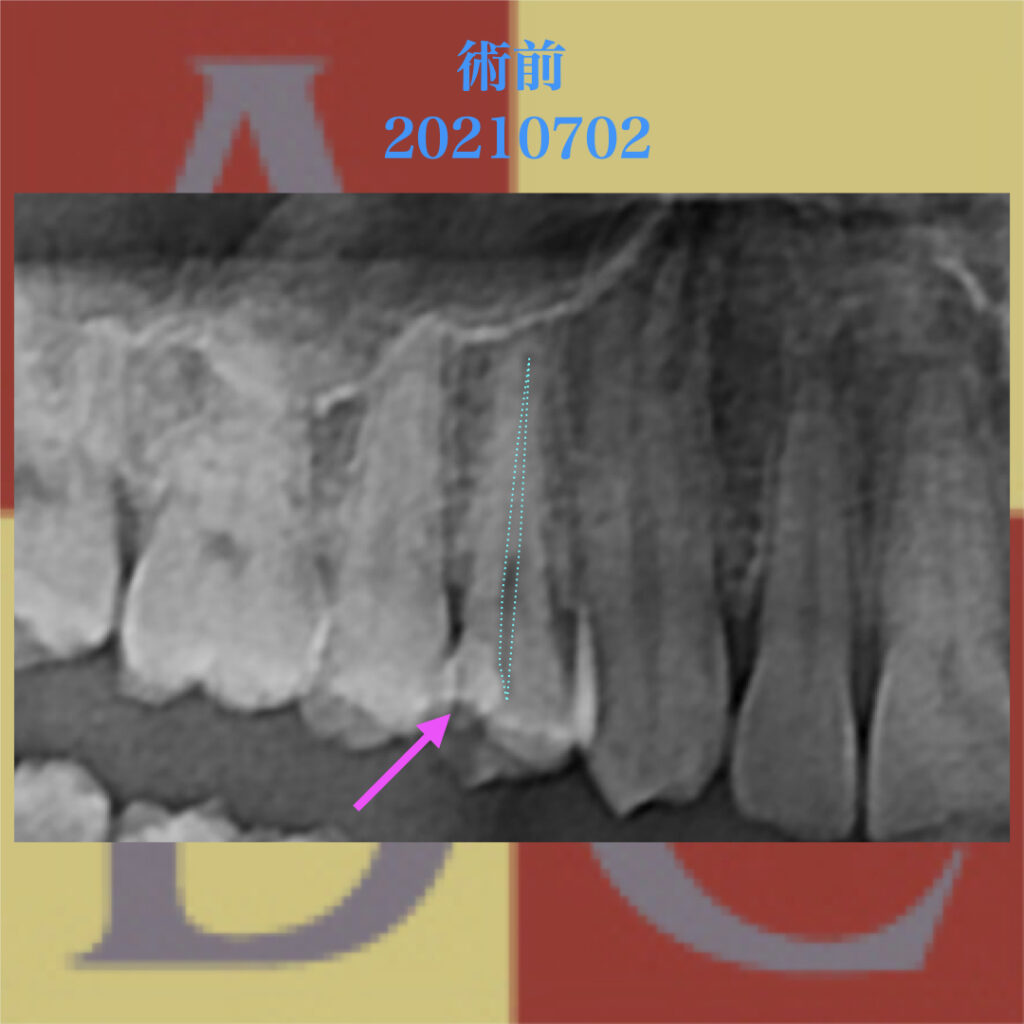

レントゲン像にて、ピンクの矢印に示された白い不透過像が浮いたCR

青い点線の部分が歯髄で、近接したCRが確認される。

コンサルテーションの結果、既に壊死している可能性もあるが隔壁作成後、

バイタルパルプセラピー(VPT)を行うこととなった。